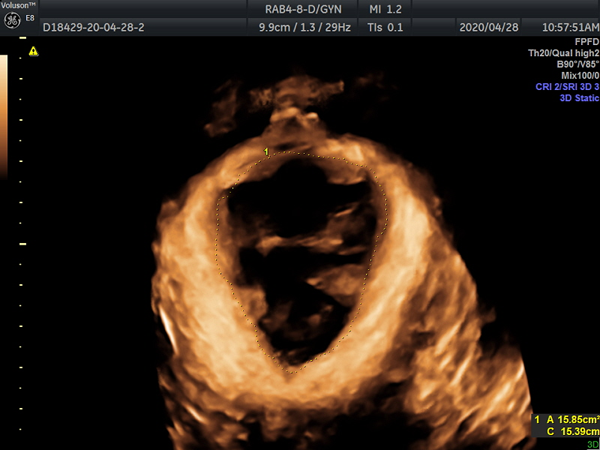

询问完病史,根据患者主述,值班大夫赵云初略判断患者可能是盆底功能障碍性疾病,建议患者行“盆底超声检查”,最终通过三维/四维超声确诊了患者的病症--GreenIII型膀胱膨出,盆底肌松弛引起的盆底功能障碍性疾病之一。这个病会引起尿潴留,导致反复泌尿系感染,病因找到了,患者被建议去我院妇科寻求帮助,下一步治疗方向有了,患者对我院工作人员连声道谢。

病因主要是妊娠、绝经后雌激素水平下降等引起盆底支撑结构损伤、松弛及功能障碍,目前在我国发病率较高。准确诊断的基础就在于对盆底结构及功能的准确认识,很多时候单纯的临床普通检查并不能获得盆底解剖以及功能改变的详细信息。 而盆底超声通过盆底组织的二维及三维/四维超声检查,获得盆底完整的声像图,可以比较直观的显示盆底各脏器的空间关系并明确诊断。

盆底超声不但可以直接观察盆底变化情况,而且膀胱移动度、尿道倾斜角、膀胱后角、尿道内口漏斗是否形成、子宫有无脱垂、直肠有无膨出、有无肠疝、肛门括约肌及肛提肌有无损伤等还可作为盆底情况客观影像学指标。